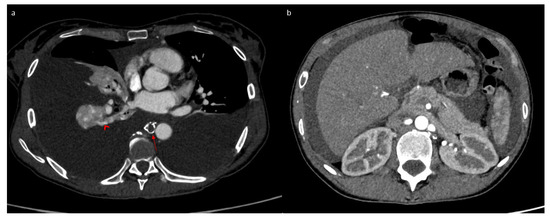

2. Case Report